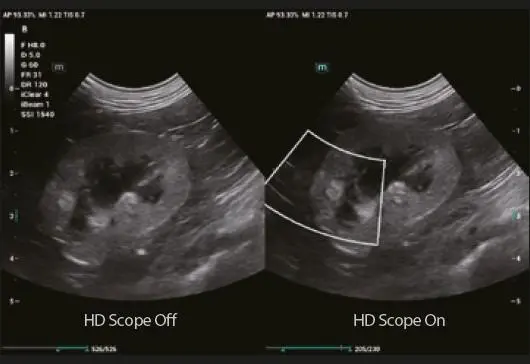

HD Scope

Чрез обработка на данните за канала, събрани от платформата ZST+, HD Scope може да подобри детайлната информация и контраста на изображението в конкретна област.

HD Scope

By processing channel data multiply and retrospectively, HD Scope can improve the detail information and image contrast on specific area maximally.